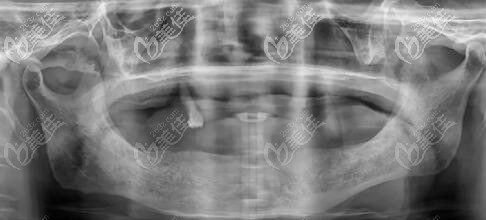

高老師種牙前的CT片▲

高老師做上半口6顆、下半口4顆種植牙后的CT圖片▲